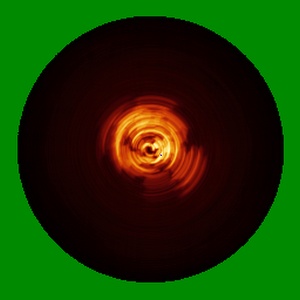

Cryo-EM structure of alpha-synuclein singlet filament from Juvenile-onset synucleinopathy

Helical reconstruction2.0 Å

Sample: Alpha-synuclein singlet filament extracted from the human brain with JOS